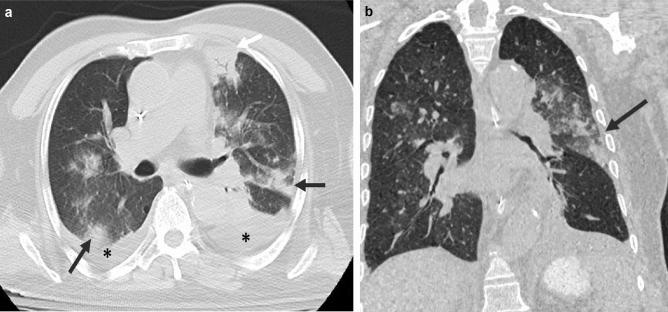

The typical HRCT findings were seen in 50 scans (65.8%) out of total positive ones; 44 (77.2%) with positive RT-PCR results and 6 (31.6%) with negative results. The peripheral disease distribution was seen in 86%, multilobe involvement in 70%, bilateral in 82%, and posterior in 82% of the 50 scans. The ground glass opacities were seen in 50/74 (89.3%) of the positive RT-PCR group. The recognized GGO patterns in these scans were: rounded 50%, linear 38%, and crazy-paving 24%. Using RT-PCR as a standard of reference, chest HRCT scan revealed a sensitivity of 68.8% and specificity of 70%.

The commonest HRCT findings in patients with COVID-19 pneumonia were peripheral, posterior, bilateral, multilobe rounded ground-glass opacities. The performance of HRCT scan can vary depending on multiple factors.

在所有阳性扫描中,50次扫描(65.8%)出现典型的HRCT表现;RT-PCR结果阳性的有44次(77.2%),阴性的有6次(31.6%)。在50次扫描中,86%的病例出现外周病变分布,70%出现多叶受累,82%为双侧受累,82%为后部受累。在RT-PCR阳性组的74例中,50例(89.3%)出现磨玻璃影。这些扫描中公认的磨玻璃影模式为:圆形占50%,线性占38%,铺路石样占24%。以RT-PCR作为参考标准,胸部HRCT扫描的敏感性为68.8%,特异性为70%。

新冠肺炎肺炎患者最常见的HRCT表现为外周、后部、双侧、多叶圆形磨玻璃影。HRCT扫描的性能可能因多种因素而异。